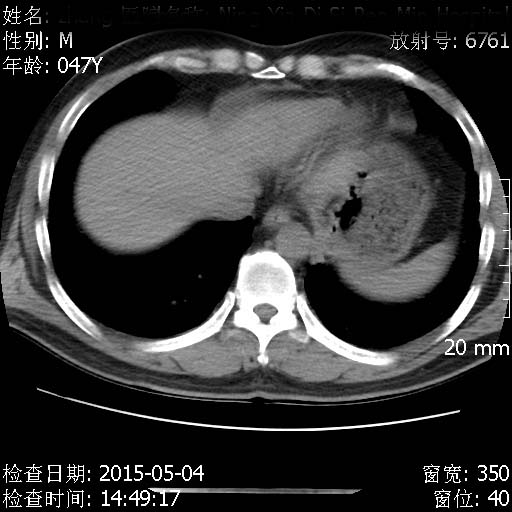

CT50379:男性 47岁 间断咳嗽3月 纵膈、肺门多发增大淋巴结。

结节病

转移瘤可能性大

临床大夫反馈,说外院纵膈淋巴穿刺,考虑结核。我还是有点怀疑这个结果。

双肺 及纵隔多发转移可能性大,结节病不除外,建议进一步检查。

双肺多发结节,肺门纵隔多发淋巴结肿大。考虑1.肺结节病 2.转性肿瘤。

考虑肺结节病

双肺 纵隔多发转移。